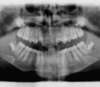

Panoramique